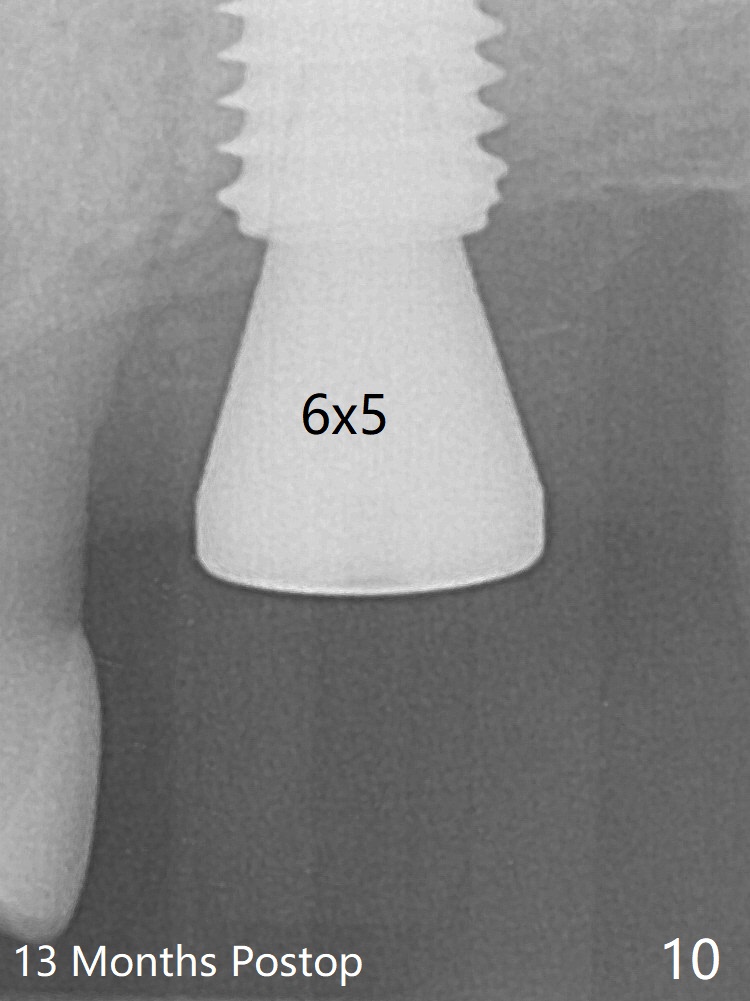

Although the buccal (Fig.1 (mesial view of the extracted tooth #15): B) root is larger than the palatal (P) one, the palatal socket is larger than the buccal one (Fig.2 white area) because of the bone loss of the former. For better restoration, osteotomy (Fig.2 red line) is initiated in the buccal slope of the septum (S) so that the final osteotomy is in the middle of the whole socket (Fig.3 red box). In fact a 3 mm stopper is not used because of the slope and the clumsy stopper. Stopper would be indicated if the bottom of the bone were flat. At first a 4x10 mm dummy implant is placed with stability (Fig.4). After further osteotomy and sinus lift (Fig.6 red dashed line: sinus floor), a 5x10 mm implant is placed with 30 Ncm, followed by insertion of a 5.2x8(2) mm temporary abutment (Fig.5,6). The latter holds an immediate provisional and Vanilla Graft/Osteogen (Fig.7 *) in place (^: distal crestal bone). Although the bone looks normal around the implant 7.5 months postop (Fig.4), the implant is unstable, probably due to the large preexisting defect. In contrast the implant placed at the healed site of #3 is stable 6.5 months postop. The 8x5 mm healing abutment that dislodged for 1 day could not return. A 6x5 mm one is used; it appears that the bone density mesial and distal to the implant is low (Fig.9 *). The implant looks normal and is stable 13 months postop (Fig.10). A 5.7x5.5(5) mm cementation abutment is placed for a provisional (progressive loading, Fig.11). There is no pain associated with the provisional for mastication. Impression is taken 7 days later. The patient has pain when the permanent crown is cemented. It appears that the implant does not osteointegrate and should be removed. A 6x14 mm tissue-level implant will be immediately placed following a 5 and 6x14 mm taps and bone graft and PRF (Metronidazole). In fact there is no pain when the existing abutment is torqued at 35 Ncm 1 year 8 months postop (Fig.12). The mesiogingival portion of final restoration (Fig.13 arrowheads) should be bulky so that the gingival embrasure (red dashed line) is minimal to reduce food impaction.